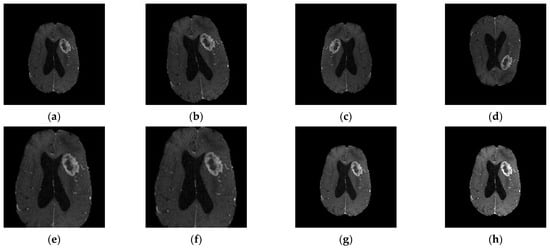

| Sequence | Sequence Characteristics | Main Clinical Distinctions | Example * |

|---|---|---|---|

| T1w | Uses short TR and TE [64] |  | |

| T2w | Uses long TR and TE [64] |  | |

| ceT1w | Uses the same TR and TE as T1w; employs contrast agents [64] |

|  |

| FLAIR | Uses very long TR and TE; the inversion time nulls the signal from fluid [67] |  |